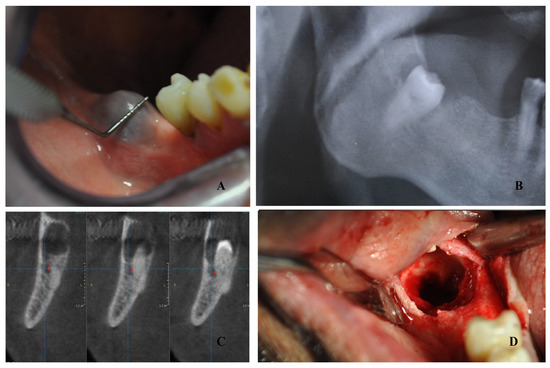

2. Case Report

| Chisci et al. | 2024 | 81 | Male | Bleeding | Dabigatran | Dentigerous cyst related to impacted lower third molar | Cyst enucleation and tooth extraction | - |